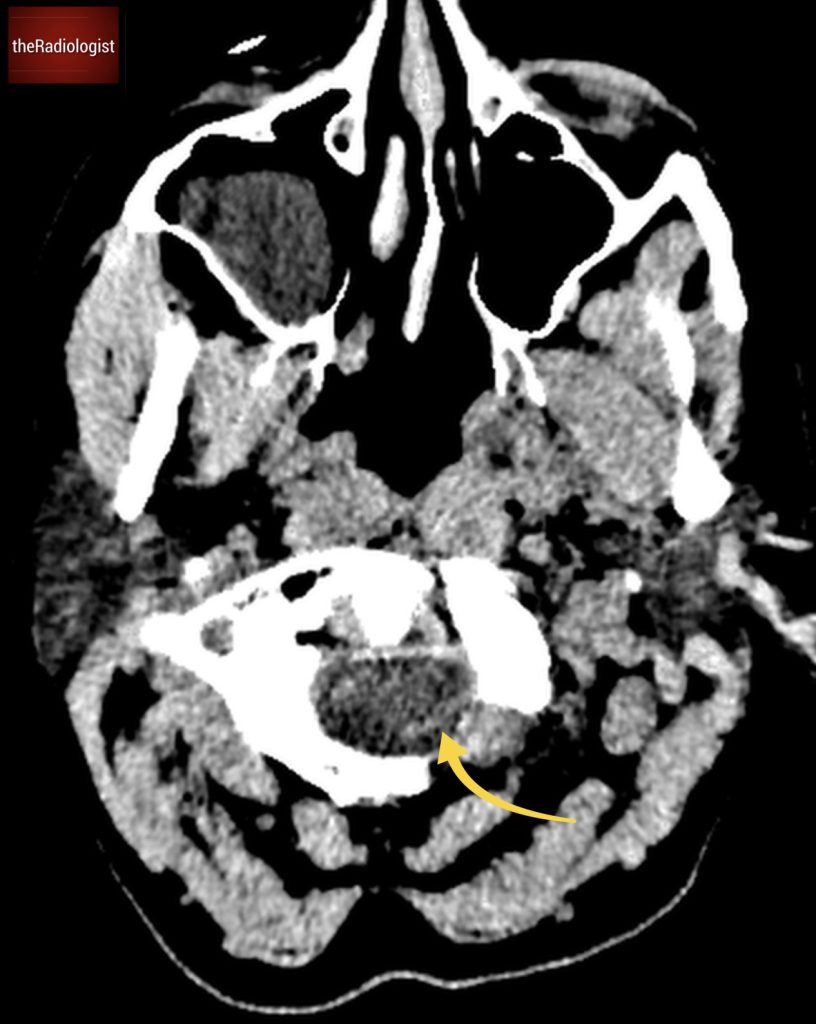

Due to pain the patient could only tolerate a few STIR sequences so we don’t have a complete scan but have a look at this axial STIR sequence below. We have high STIR signal within the right psoas with locules suggesting abscess formation.

Have a look at this axial STIR image from the MRI scan. Here we have high SITR signal within the right psoas with locules suggesting abscess formation.

If we look at a lateral STIR sequence of the lumbar spine, we can see high signal in the lateral aspect of the L3-4 disc which is continuous with the abscess formation within the right psoas. This highly suggests a spondylodiscitis as the primary pathology leading to secondary psoas abscess.

When we scroll through this sagittal STIR sequence of the lumbar spine we will see high signal within the L3-4 disc adjacent to the right psoas abnormality.